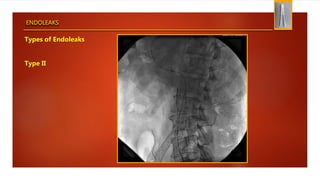

ENDOLEAKS

Types of Endoleaks

Type II